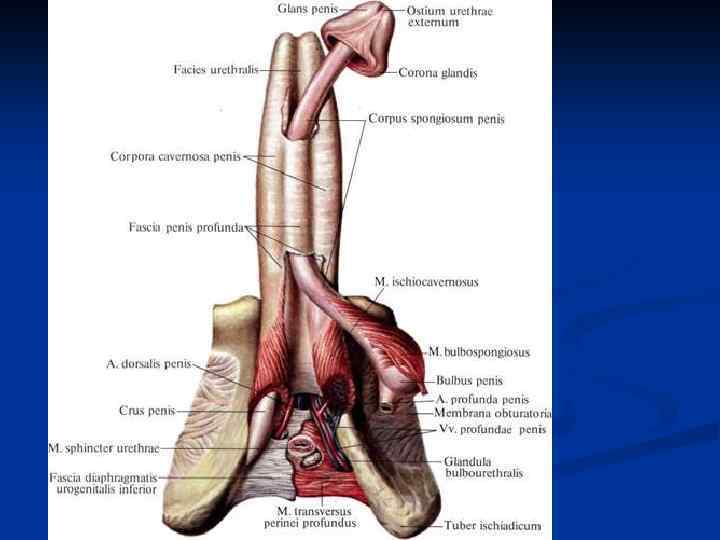

Половой член, penis: 1. Головка, glans penis 2. Тело, corpus penis 3. Корень, radix penis

Половой член, penis: 1. Головка, glans penis 2. Тело, corpus penis 3. Корень, radix penis